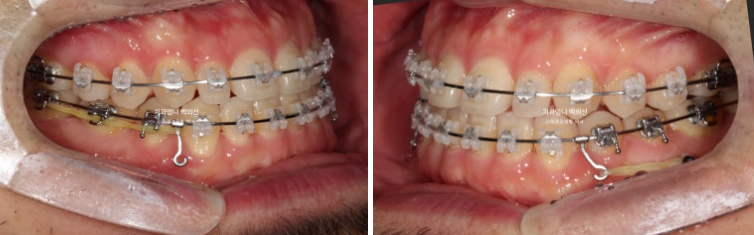

치료 시작 10개월차 모습입니다. 교정용 나사인 미니스크류를 아래쪽에 심고 사랑니 공간으로 밀어냅니다.

24.11

치료시작 1년 5개월 차 치료를 마무리 했습니다.

25.06